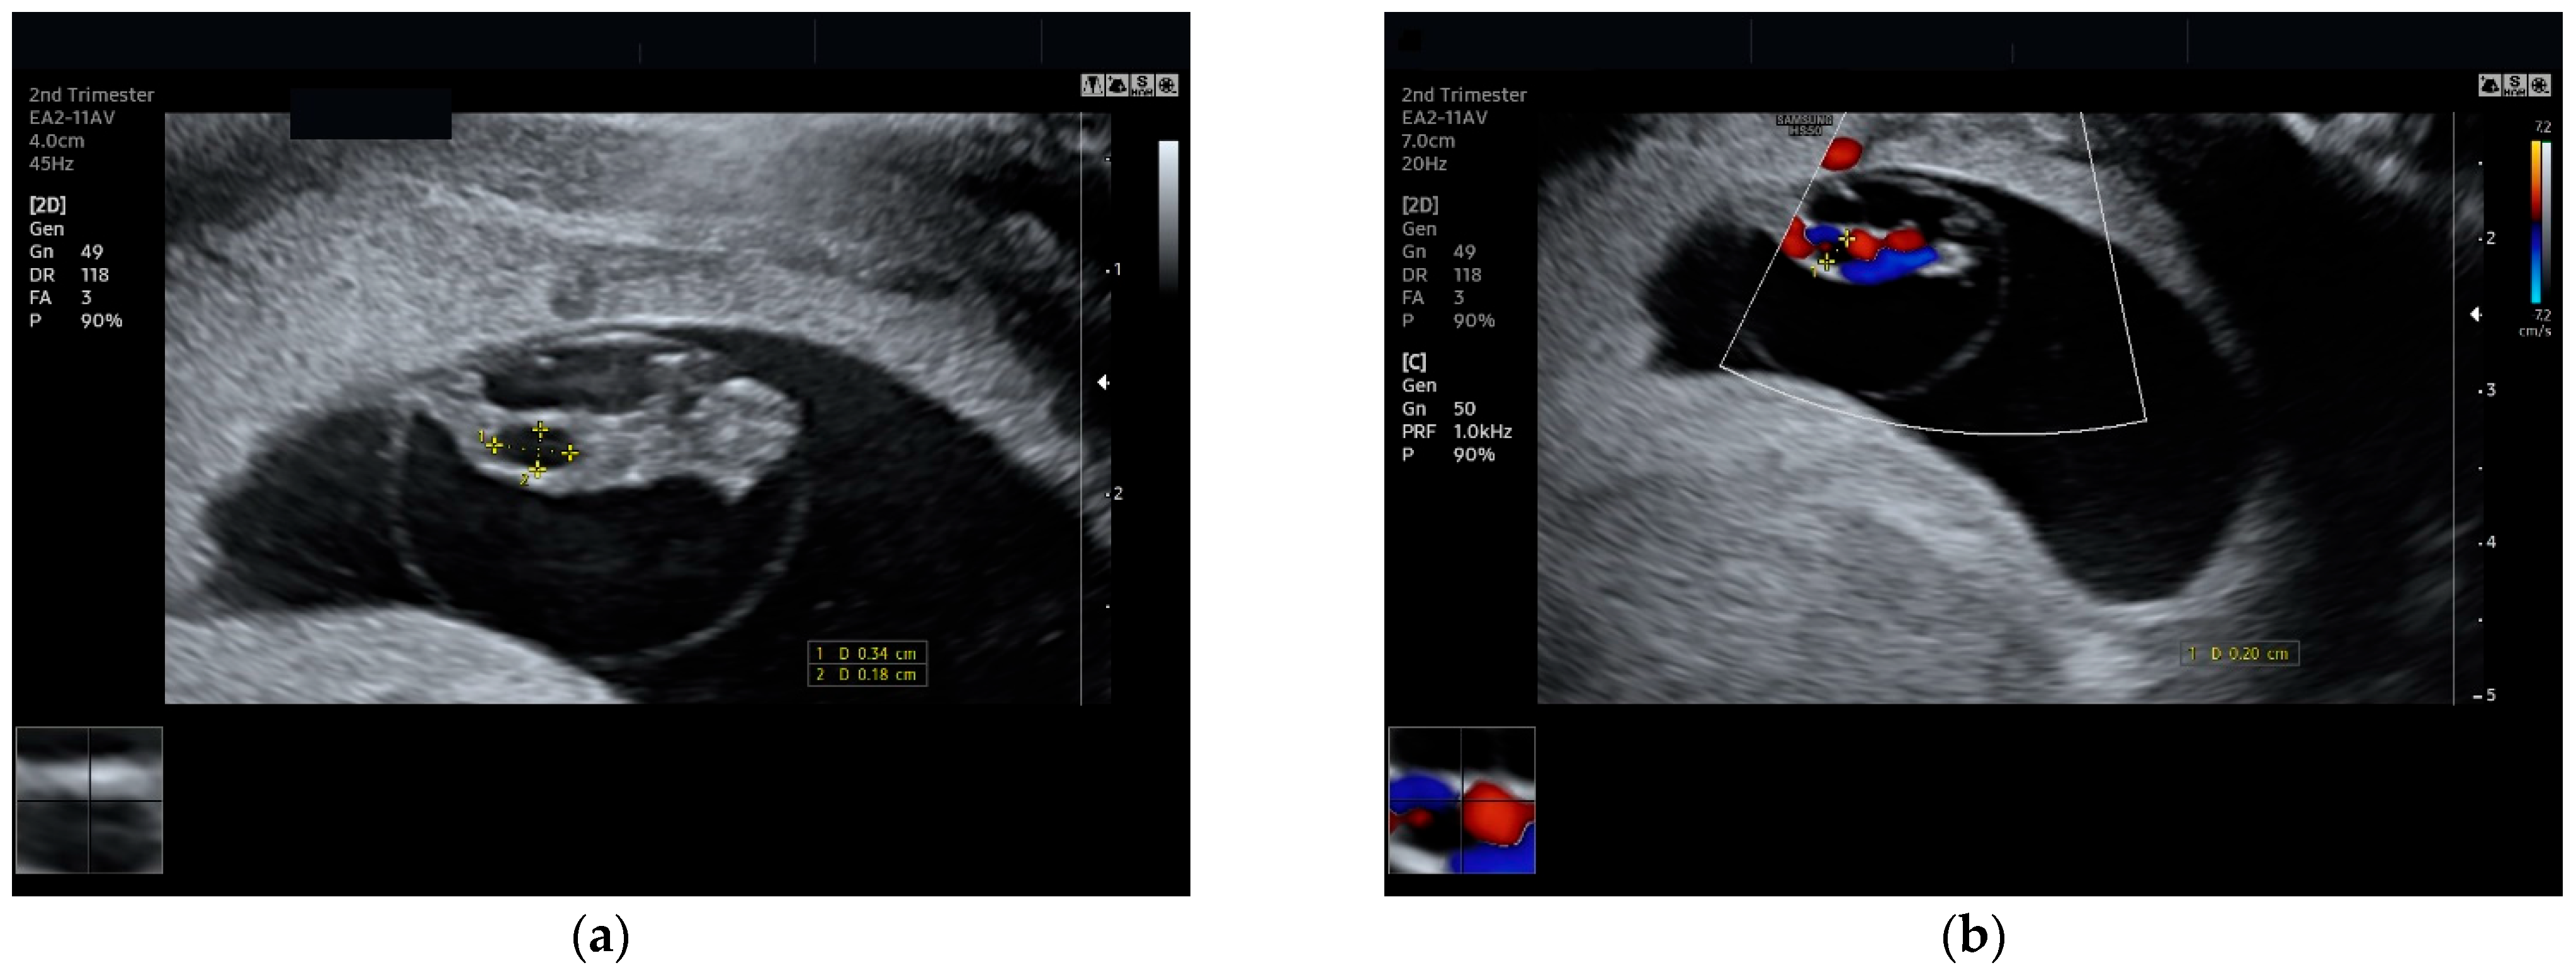

3.1. Case Report